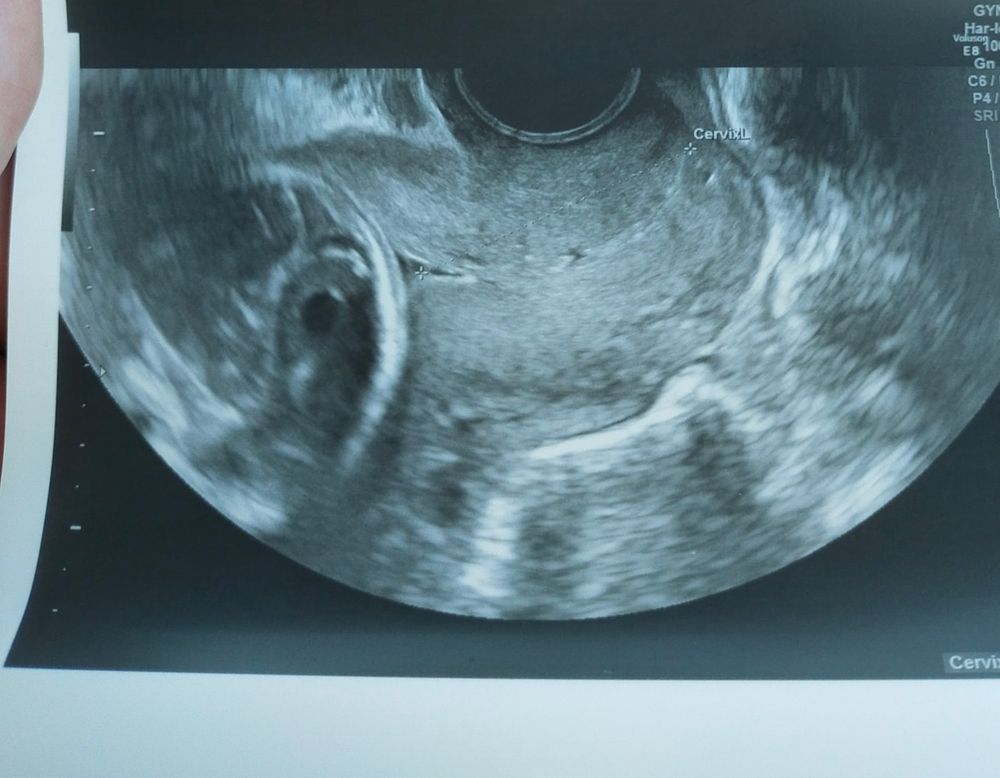

HappinessInMind, спасибо большое) А это какой срок? Вроде после 30? У меня вот такая дырочка. Изображение

В 15 недель шейка 38 мм и расширение зева 2 мм, врач узи спросила ставлю ли я какие то свечи,я в тот момент клиндомицин вставляла, ну она сказала,что ничего страшного, в 18 недель пришла снова шейка 36 и зев сомкнут, сказала,что все отлично и врачи не говорят,что у меня тенденциия к ИЦН

У вас хорошая длина сомкнутой части, поэтому вам и говорят, что всё нормально и скорее всего нормальной структуры. Просто наблюдайте, раз в 2 недели это нормальный период, если сильно переживаете, то можете раз в неделю походить

Короче, мое мнение, что внутр зев 5 мм это много

Че-то я зашивалась при внутр зеве 2 мм (хотя мне НС говорила, что до 10 мм не очень страшно). Длина у меня юыла 35 мм.